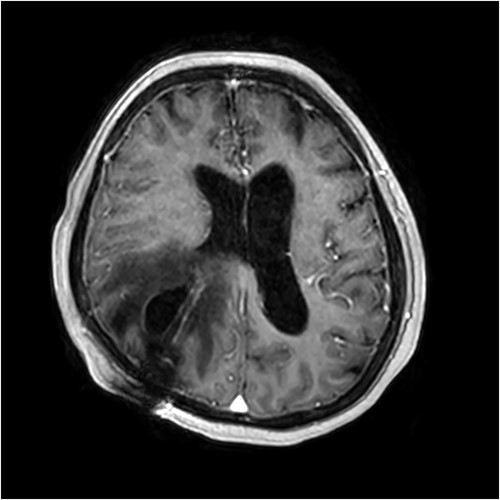

On Day 5 of her rehabilitation admission (29 days after the shunt was inserted), a rapid response call was initiated for reduced level of consciousness (Glasgow coma scale 3). An urgent CT brain was performed which showed an extensive area of low density in the right parietal and posterior frontal lobe adjacent to the entry of the ventricular shunt, with some subarachnoid blood in the adjacent sulci. The patient was transferred back to the acute hospital, where an urgent magnetic resonance imaging (MRI) scan demonstrated a likely CSF cyst around the shunt catheter, with subacute haemorrhage within the cyst (Fig. 2). An abdominal CT scan showed no evidence of distal shunt obstruction. A surgical revision of the ventriculoperitoneal shunt took place the next day. Brisk flow was confirmed in the distal catheter without its Codman® Certas valve connected. A small amount of CSF egress was found around the ventricular catheter, and a replacement proximal catheter was inserted and connected to a new Certas valve.

Contrast-enhanced T1-weighted MRI scan showing presence of the intraparenchymal cyst and surrounding vasogenic oedema.